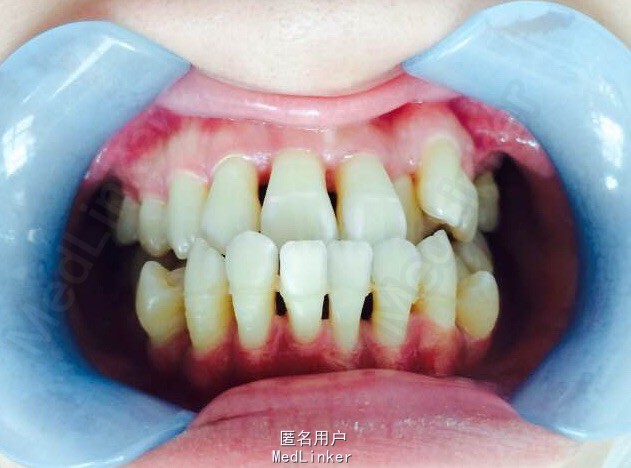

女,23岁,重度侵袭性牙周病,有家族遗传性

讨论:牙周治疗处于维护稳定阶段,下合2—2牙槽骨吸收至根尖1/3水平,是否适合正畸?下个前牙的保留问题